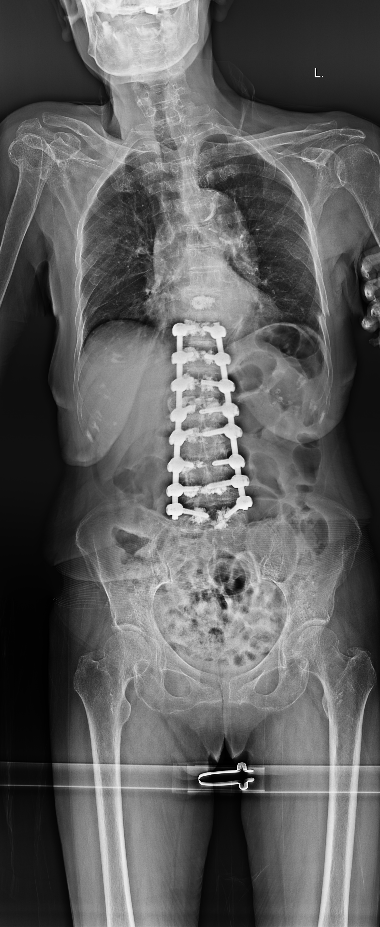

术前(左)和术后(右)对比: 术后脊柱后凸矫正,骨折椎体强化固定

手术过程顺利,术后快速康复,实现早期活动

彭旻副主任团队为吴婆婆成功实施了 “后路脊柱后凸截骨矫形、骨水泥钉内固定、后外侧融合术”。术后,在加速康复理念的指导下,吴婆婆恢复顺利,腰背部疼痛显著缓解,术后第二天即可在支具保护下坐起,并逐步开始下地站立行走,避免了长期卧床带来的并发症。